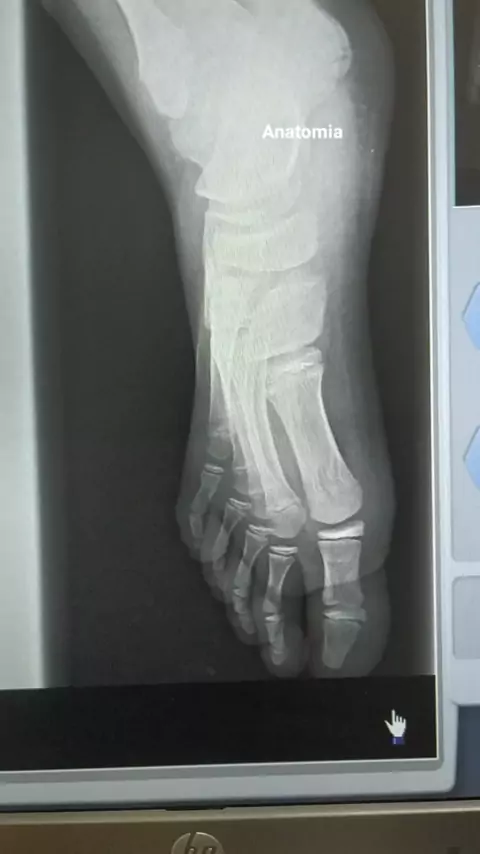

#anatomia #radiologia